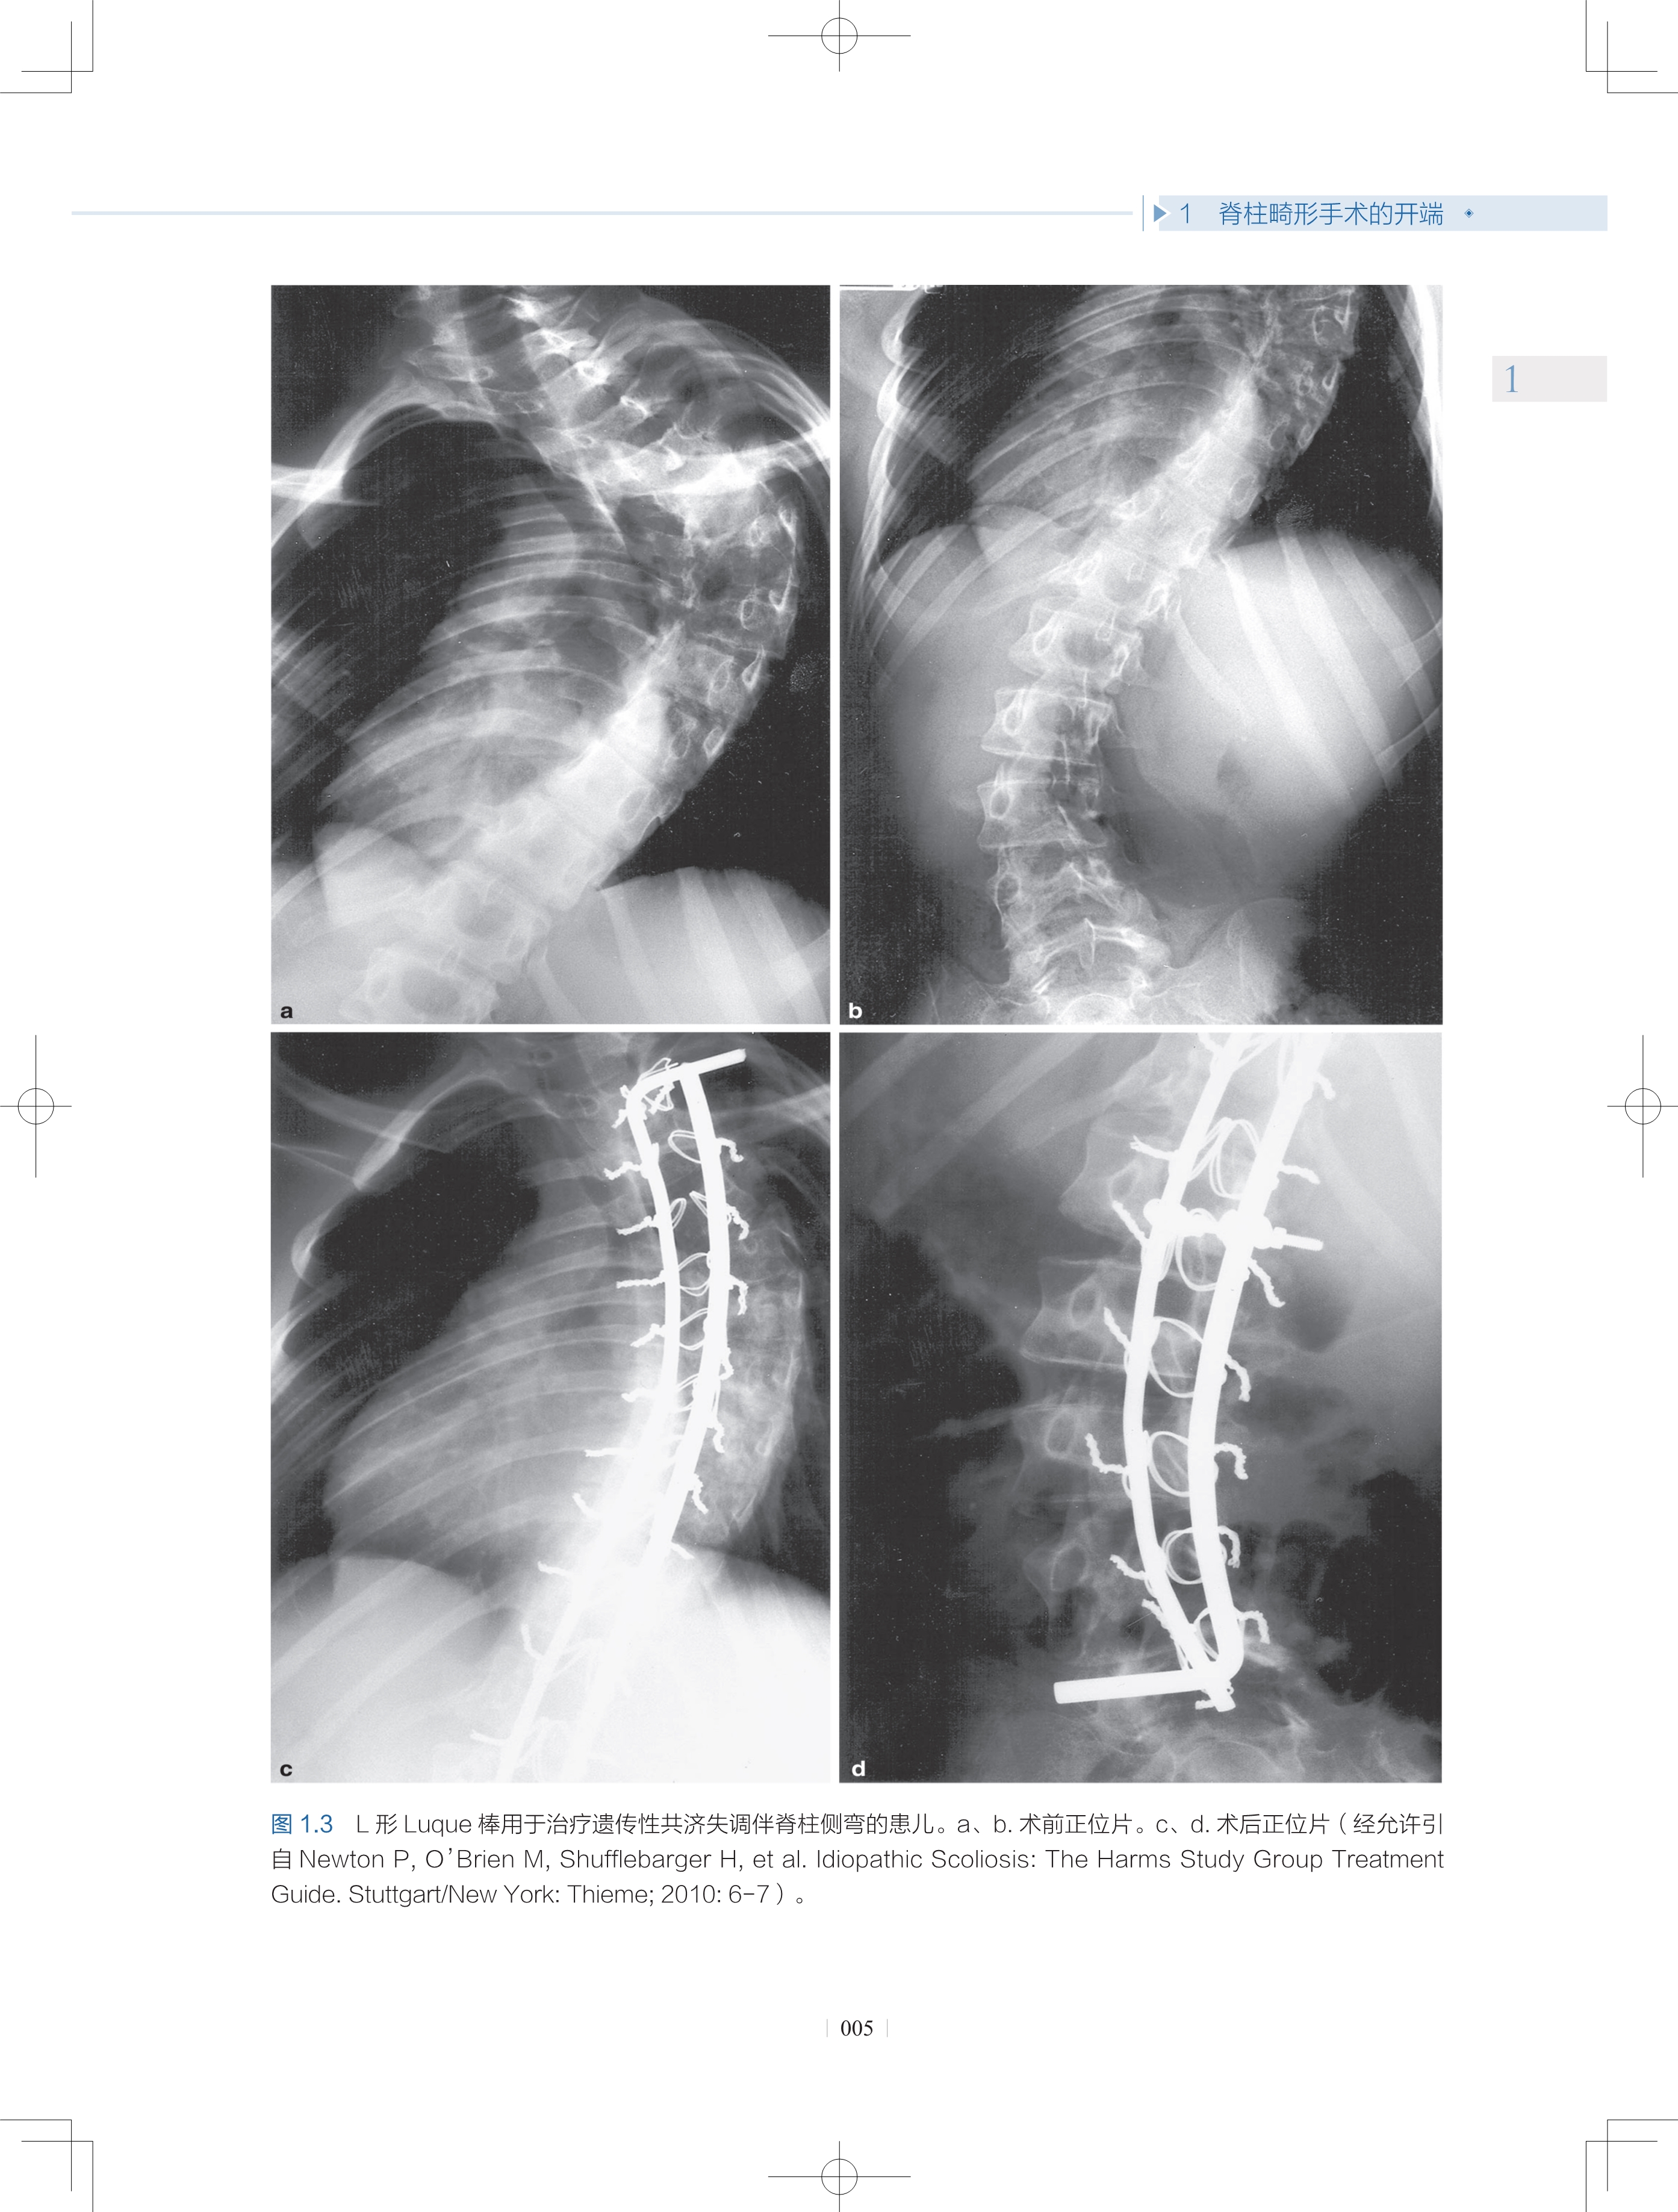

1 脊柱畸形手术的开端

1.2 后路固定